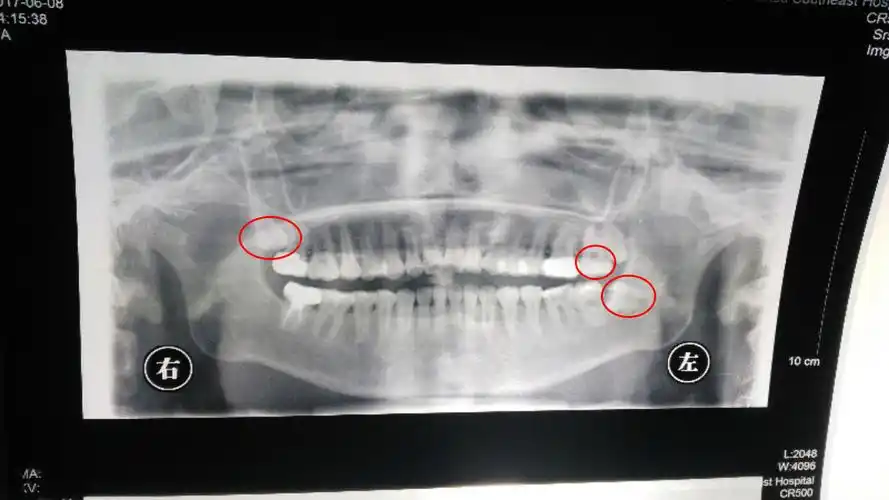

x光全景片.jpg